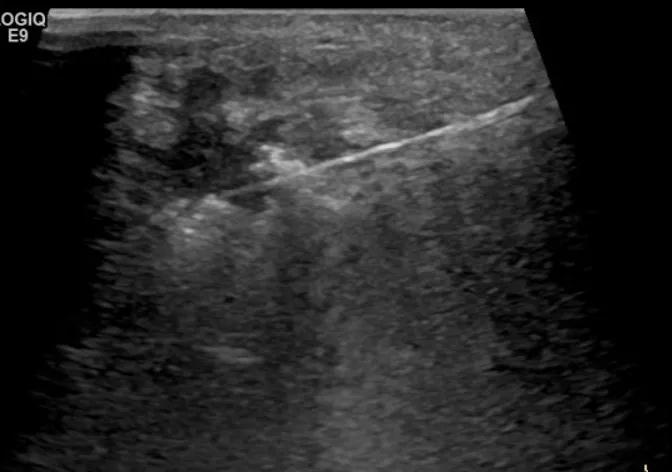

第二例是食管癌患者,术后半年余锁骨上固定淋巴结可触及肿大,疼痛非常明显,系统治疗后无缓解,患者希望通过局部处理缓解症状。造影显示强化信号明显,结节部分区域坏死,故主要针对强化区域从后向前的逐层的消融,皮下进行液体隔离减少烫伤。热消融后影像显示血流增强消失,弹性、硬度增高,一个月后复查显示充盈缺损,完全消融,疗效远超预期。

(病例2图例)